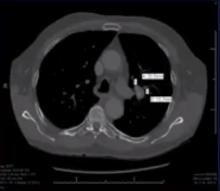

In this video, the authors present a robot-assisted lingula-sparing left upper lobectomy, using segmental plane identification with near-infrared fluorescence imaging. During this procedure, the arterial and venous vasculature, along with the bronchial segments to the apico-posterior and anterior segments of the left upper lobe, are identified and divided. Once the upper divisions have been devascularized, 5-10 mg of indocyanine green is infused intravenously. Using near-infrared fluorescence imaging technology, the lung parenchyma is inspected. The well-vascularized lingula fluoresces brightly in contrast to the devascularized apico-posterior and anterior segments. The intersegmental plane separating the lingula and upper divisions is easily identified, which facilitates this lingula-sparing sublobar resection.